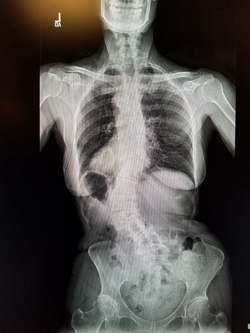

My scoliosis was found when I was 16 years old. I had problems with my hips hurting but I had gotten along since then by going to a physical therapist now and again. It progressed in degrees after I turned 65. It held at about 45 degrees for several years and then quickly got worse until I had to quit hiking Phoenix South Mountain. Then it stopped me from working. I had to find a surgeon to help me.

The surgery was 12 hours long. The way Bob understood it was that my blood was replaced 3 times. I did not wake up for 3 days. I did not know then that they had even done the surgery. When I did, Bob had to feed me. My hands still seem to drop things. My left leg and abdomen hurt the worst. I am told that my body has to get used to the changes. There were 63 staples down my back. I was at Barrow ( St Joseph) for 10 days I believe. The surgeon did a wonderful job and spared all the nerves.

My year is up and I have had my 1 year x-rays and Surgeon appointment. Everything looks to be holding. I guess you would say that I no longer have scoliosis. I do still have that cardboard feeling in the muscles of my back. I mentioned to Dr. Kakarla that when I try to lift a gallon of milk the back goes into spasms and gets tighter. He decided that I needed another 30 sessions at physical therapy to make my upper body and legs stronger.

I still am doing the 4 mile hike. So with 3 times a week at PT and the hike my days are busy. Hope we can get started with our summer by Easter. Here are two views of my spine at my one year checkup.